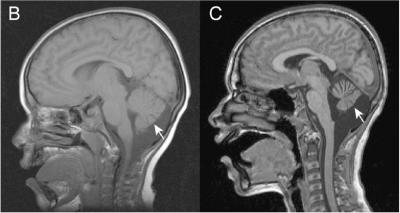

In their study, Morrow's team was able to quantify the most frequent symptoms specific to CS. These include moderate to severe intellectual disability, epilepsy, difficulty or inability walking and talking, attenuated head and brain growth, and hyperactivity. Boys sometimes exhibit other specific symptoms – including autism-like behaviors, low height and weight, acid reflux, and regressions in speech and motor skills after age 10 – that the researchers include as secondary proposed diagnostic criteria. A third of the boys also had potentially neurodegenerative problems such as atrophy of the cerebellum.